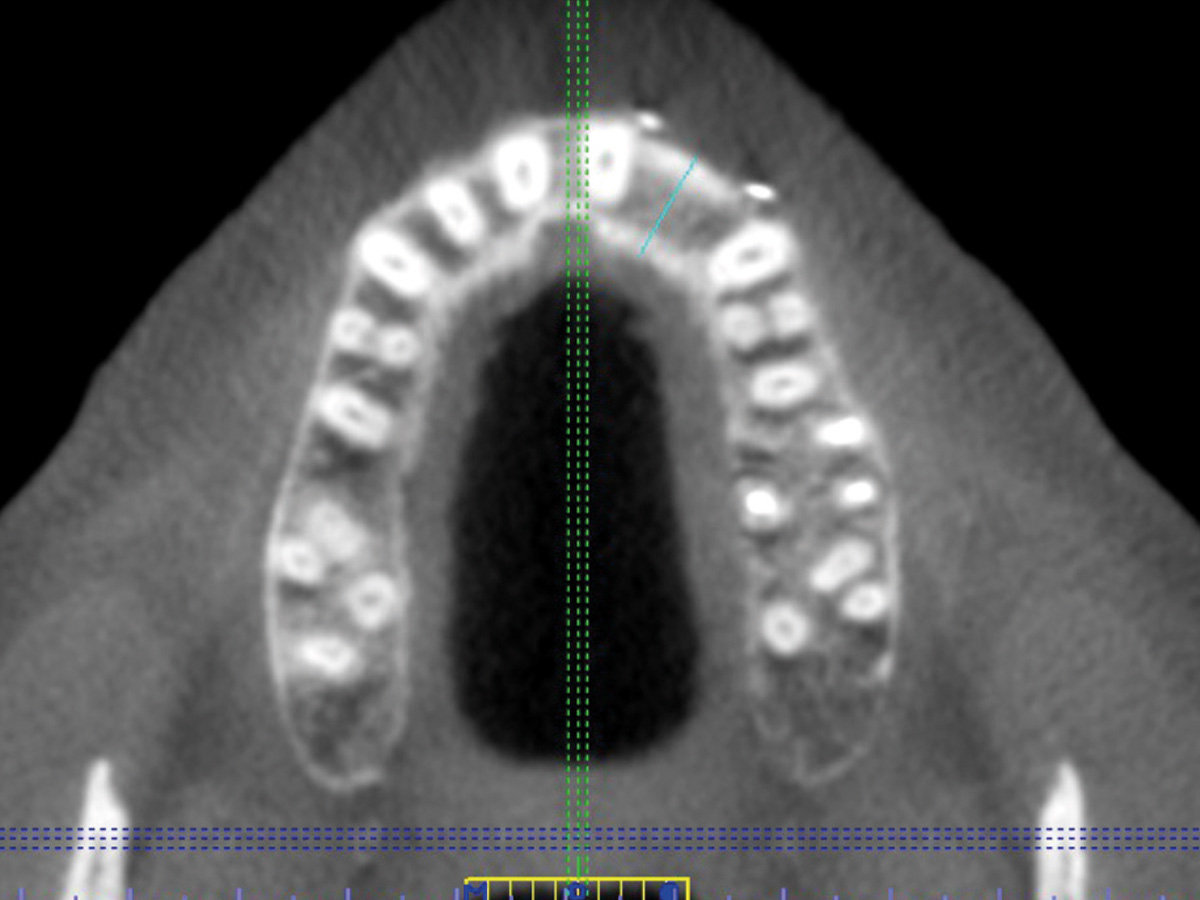

Abbildung 9

Regenerierter Bereich im DVT. Die Knochenbreite beträgt jetzt 10,3 mm. Man kann deutlich die Spongia von der Kortikalis unterscheiden.